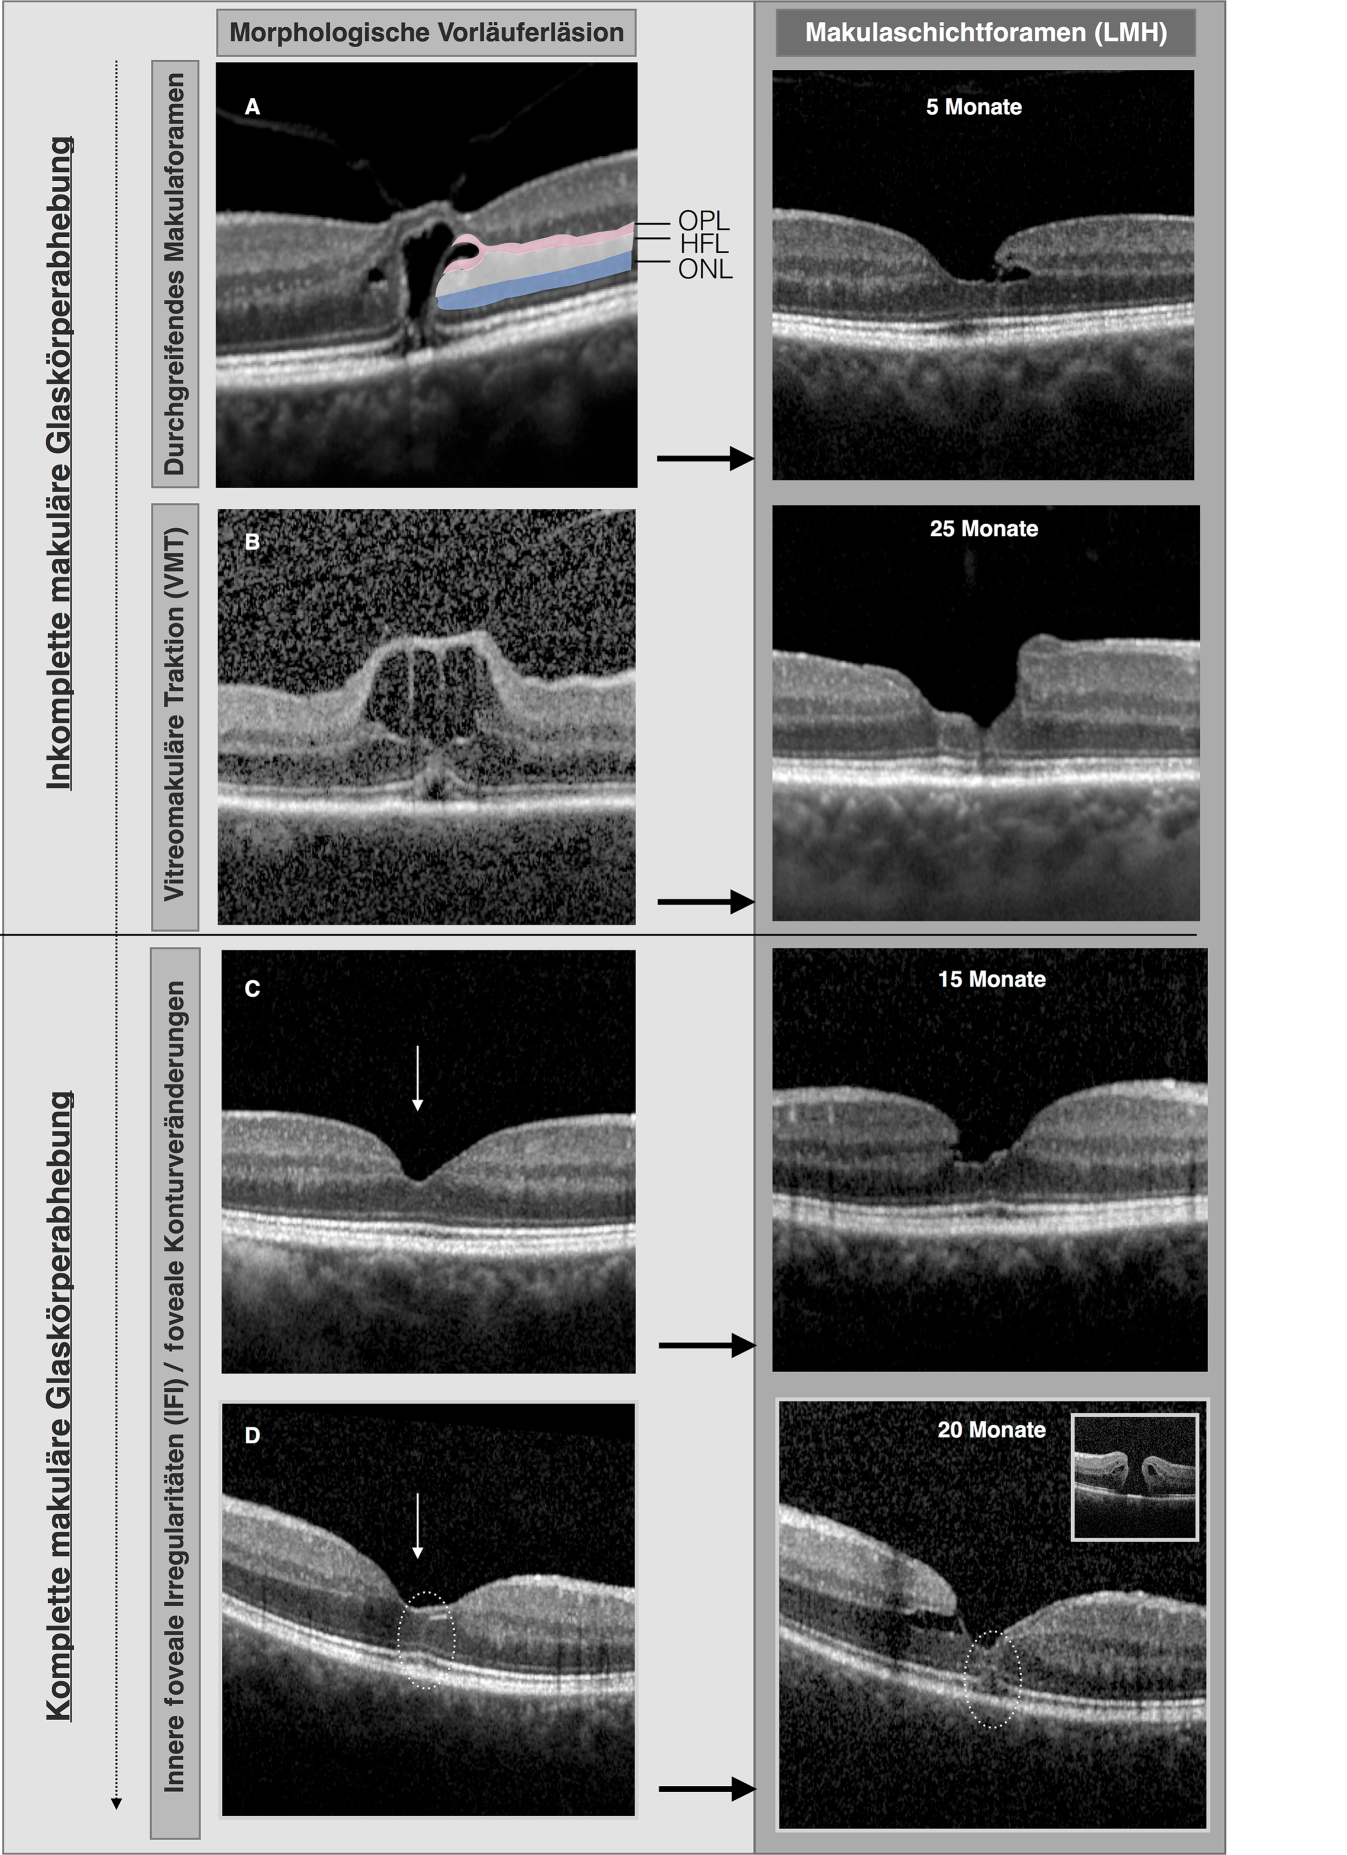

In einer Serie von 4 gesammelten Fällen werden in Abb. 4 exemplarisch Spontanverläufe dargestellt, die die mögliche Vorläuferläsionen eines LMHs vor und nach einer makulären Glaskörperabhebung darstellen. Anhand der OCT-Befunde vor der makulären Glaskörperabhebung lässt sich die traktionsbedingte Schädigung des Müller-Zell-Konus mit anschließender Spaltbildung auf Höhe der OPL (äußere plexiforme Schicht)/HFL (Henle-Schicht) unmittelbar visualisieren. Nach erfolgter makulärer Glaskörperabhebung kann sich ein stattgehabter traktionsbedingter Schaden der fovealen Architektur in fovealen Konturveränderungen reflektieren. Sie können ein dezenter, aber wichtiger retrospektiver Biomarker für eine „spontan gelöste“ traktive Makulopathie nach erfolgter makulärer Glaskörperabhebung sein und werden von unserer Arbeitsgruppe gleichzeitig als früher prospektiver Biomarker für die Entstehung eines LMH mit weiterer Progression zu einem FTMH nach erfolgter Glaskörperabhebung gewertet (innere foveale Irregularitäten [IFI]) [27]. Im Jahr 2011 berichteten Kumagai et al. über eine signifikant höhere Inzidenz solcher fovealer Deformationen nach makulärer PVD in Partneraugen von Patienten mit einseitigem FTMH [28]. In unserer retrospektiven Kohorte fand sich eine IFI-Läsion nach makulärer Glaskörperabhebung in 23,7 % der Partneraugen von Patienten mit FTMH [27].

Abb. 4

Spontanverläufe (SD-OCT [spectral-domain-optische Kohärenztomographie]) am vitreoretinalen Übergang die in unterschiedlichen Ausprägungen eines Makulaschichtforamen münden. A und B stellen Vorläuferläsionen vor Lösung der hinteren Glaskörpergrenzmembran von der Makula dar. In C und D liegt bereits eine hintere Glaskörperabhebung im Bereich der Makula vor, wenngleich sich eine Vitreoschisis in der SD-OCT nicht ausschließen lässt. Im Rahmen der vitreomakulären Traktion in A und B kommt es zur Spaltbildung der inneren Netzhaut, insbesondere zur Schädigung auf Höhe der Henle-Schicht (HFL), sowie der äußeren plexiformen Schicht (OPL). Im Fall A kommt es zusätzlich zu einem Defekt der äußeren Körnerschicht (ONL) und der externen limitierenden Membran (ELM). Die Defekte im Bereich der OPL und der HFL gelten durch die damit verbundene Schädigung der fovealen Wand als ursächliche Läsion für die zukünftige Entstehung eines lamellären Makulaforamens (LMH) im Falle eines Spontanverlaufs. Fünf und 25 Monate nach Erstvorstellung zeigt sich in A respektive B ein LMH. In Fall A entstand das LMH aus einem Spontanverlauf eines FTMH mit entsprechender Regeneration der ONL. C und D: Es zeigen sich foveale Konturveränderungen und Asymmetrien (weißer Pfeil), die als sog. innere foveale Irregularitäten (IFI) ohne sichtbare oder ausgeprägte Traktion zu einem LMH führen können. In D lassen sich im Bereich des fovealen Dachs sowie im Bereich des zentralen Müller-Zell-Konus zusätzlich hyperreflektive Linien erkennen. Diese können als „hyperreflective stress lines“ auf einen frühen Schaden im Müller-Zell-Konus hindeuten und die Entstehung eines durchgreifenden Makulaforamens aus einem LMH ankündigen. Dies war insgesamt 27 Monate nach Erstvorstellung in D der Fall (kleines Kästchen)